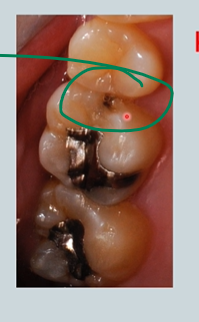

compare the distal aspect of the upper 5s and the mesial aspects of the upper 6s - what can you see?

in the black - areas within the lesion there are still areas of remineralisation

patient chipped tooth - cannot brush correctly - caries process